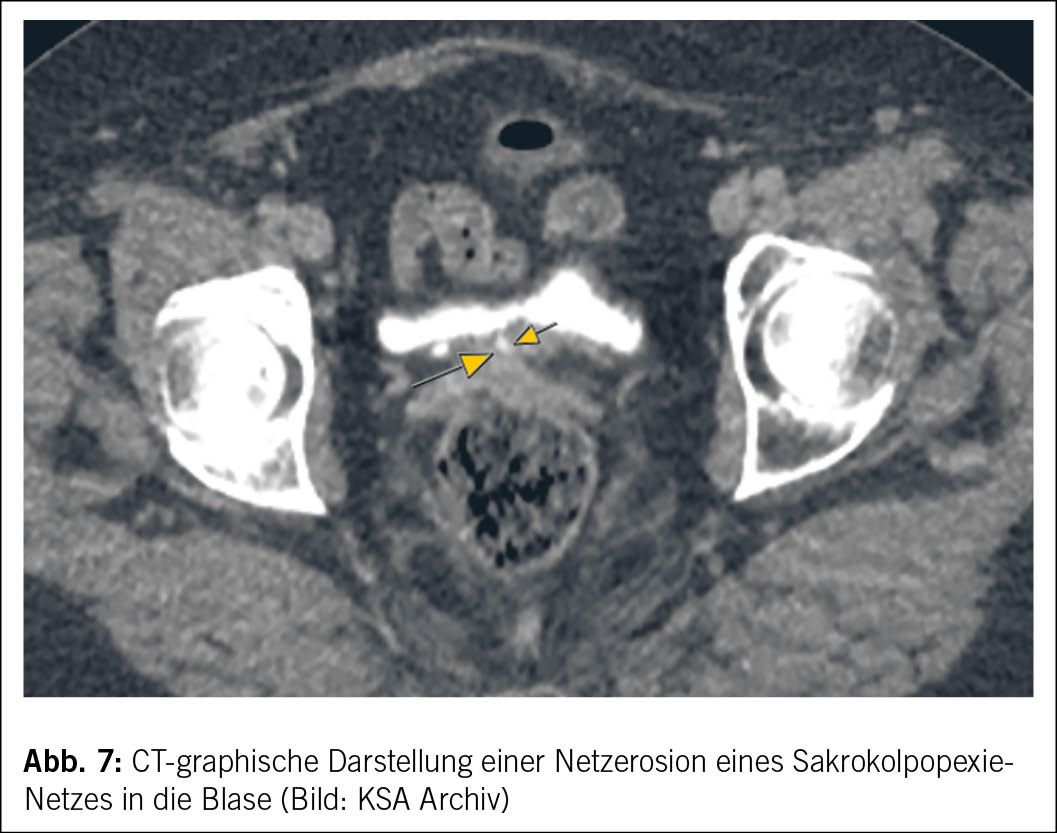

Bei Verdacht auf eine Netzerosion ist eine ausführliche Anamnese essenziell, die den ursprünglichen Eingriff, die Symptome sowie die Ziele der Patientin berücksichtigt (19, 20). Die klinische Untersuchung sollte eine Spekulum- und bimanuelle Untersuchung sowie eine Beckenbodensonographie zur Beurteilung von Lage und Ausdehnung des Netzes umfassen. Ergänzende diagnostische Verfahren wie Zystoskopie, Proktoskopie, Koloskopie oder MRT sind angezeigt, wenn der Verdacht auf Netzerosion in Blase oder Darm besteht oder die Symptomatik unklar ist (19, 20). (Abb. 7 und Abb. 8)